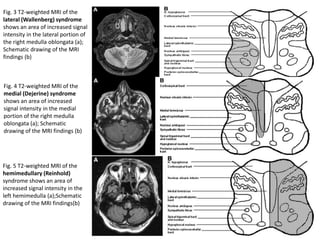

Fig. 1 T2-weighted MRI of Babinski-

Nageotte syndrome shows an area

of increased signal intensity in the

lateral portion of the left medulla

oblongata with spreading of the

lesion to the pyramidal tract (a);

Schematic drawing of the MRI

findings (b)

Fig. 2 T2-weighted MRI of Cestan-

Chenais syndrome shows an area of

increased signal intensity in the

lesion to the pyramidal tract and

sparing of the posterior

spinocerebellar tract (a); Schematic

drawing of the MRI findings (b)

Fig. 5 T2-weighted MRI of the

hemimedullary (Reinhold)

syndrome shows an area of

left hemimedulla (a);Schematic

drawing of the MRI findings(b)

Fig. 4 T2-weighted MRI of the

medial (Dejerine) syndrome

shows an area of increased

signal intensity in the medial

portion of the right medulla

oblongata (a); Schematic

Fig. 3 T2-weighted MRI of the

lateral (Wallenberg) syndrome

shows an area of increased signal

intensity in the lateral portion of

the right medulla oblongata (a);